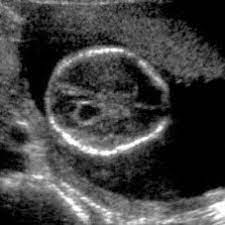

Prenatal Imaging Findings In Down Syndrome Practice Essentials Ultrasonography